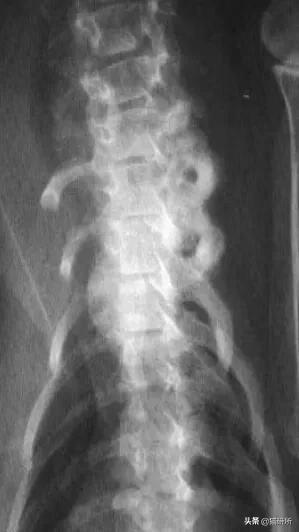

九岁去势公猫,长期以猪肝为主喂食自制食物。就诊时左前肢跛行,后出现霍纳氏综合征,两个月发展成瘫痪。

经病史检查,血液和影像学分析和以及血清维生素A浓度的测定,诊断为维生素A过量继发臂神经丛压迫。

尾颈椎和颅胸椎腹侧新骨形成